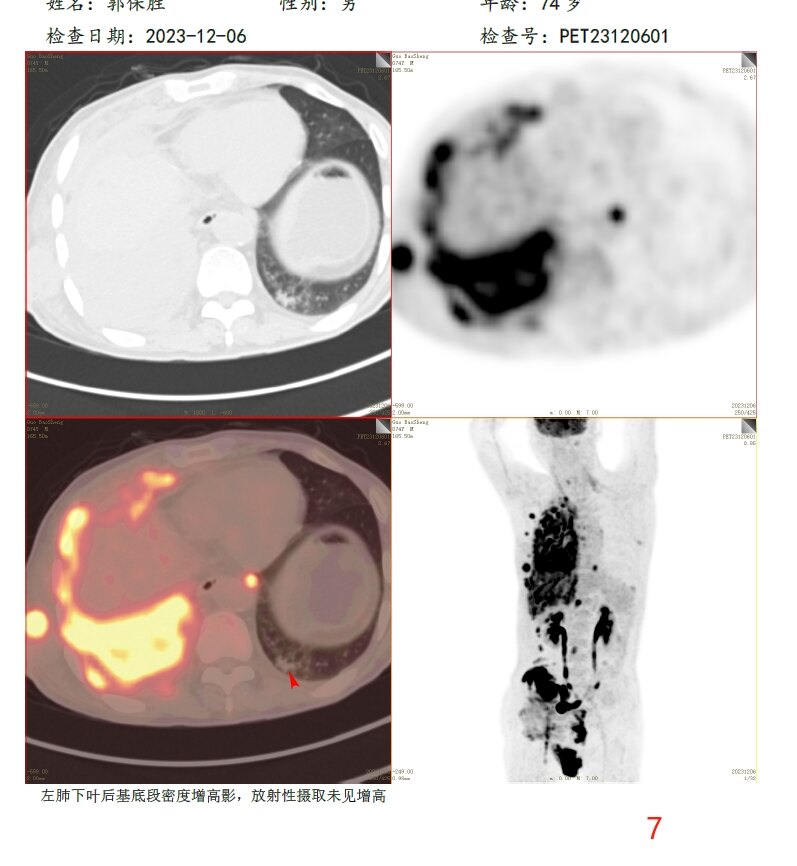

放疗前PET/CT(2023-12-06):

7